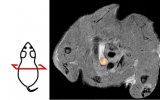

太和縣人民醫院核醫學科聯合癲癇中心成功開展皖西北地區首例PET-MRI融合圖像指導下的迷走神經刺激器置入術

2024年9月,安徽省太和縣人民醫院核醫學科成功開展皖西北地區首例PET-MRI融合圖像指導下的迷走神經刺激器置入術(VNS),標志著該院在癲癇分子影像診療領域邁出重要一步。癲癇是常見的神經系統慢性疾病,長期發作可引起神經生物學異常、認知功能下降以及嚴重的社會心理學問題。運用多模態的影像學技術精準定位致癇灶并進行神經外科手術干預是控制藥物難治性癲癇發作最有效的方法。然而,PET/MR技術對基層醫院存在較高的專業門檻和技術難度,如... 2024-11-14